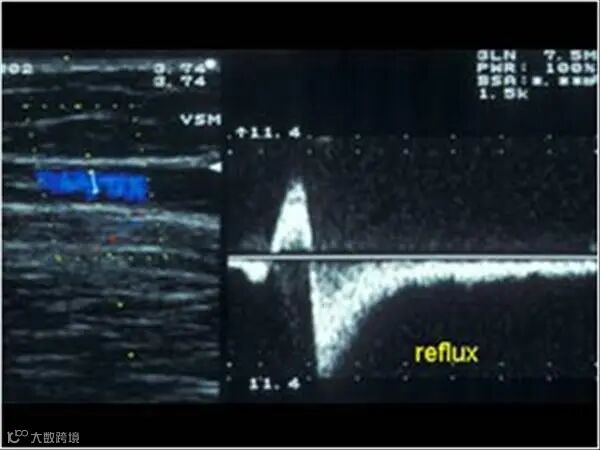

深静脉(如股静脉、腘静脉)反流时间 > 1秒 → 功能不全

浅静脉(如大隐静脉)反流时间 > 0.5秒 → 功能不全

反流源:血流开始反向的位置(需治疗)

回流点:血流恢复正常的位置(常无需处理)